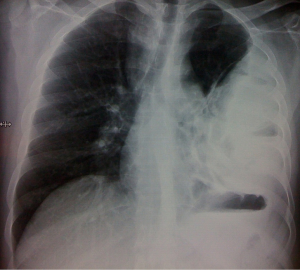

Empyema thoracis (Figures 2,3) can be a complication of pneumonia, tuberculosis or various iatrogenic pulmonary interventions. Despite widespread use of highly effective antibiotics, chronic empyema thoracis (CET) is common worldwide. Corrective procedures like tube thoracostomy, image directed catheters, thoracoscopic drainage, decortication and open drainage have all been employed with success rates varying between 10% to 90% (12). VATS has shown promising results in decortication and adhesiolysis. Perioperative bleeding and air leak are the main concerns in extensive adhesiolysis and decortication. Modern electronic chest drainage systems with suction capability are a boon as it gives the estimate of air leak, drain, helps in lung expansion and early mobility. Talc pleurodesis is employed in an effort to prevent recurrence in patients with repeated effusions.